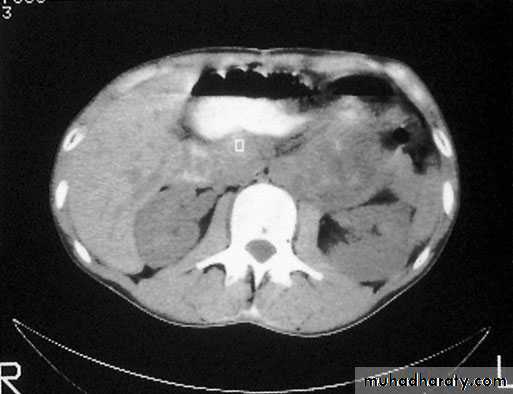

CT scan and MRI are the most useful means of detecting secondaries and f monitoring the response to therapy.Staging